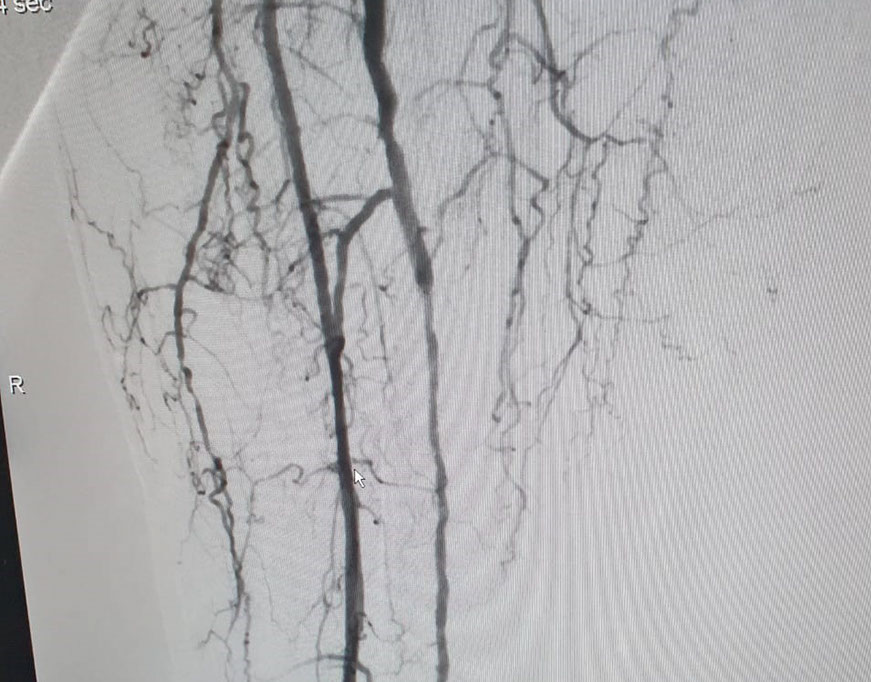

Las imágenes siguientes son previas al procedimiento y posterior se ve ambas arterias tíbiales permeables, y circulación en el pie